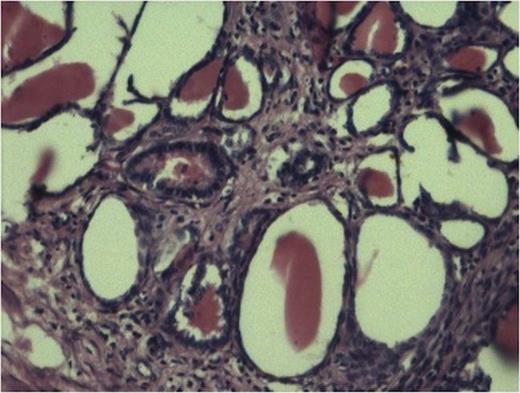

The sections from various representative areas revealed dilated pelvicalyceal system lined by metaplastic squamous epithelium and shows changes of chronic pyelonephritis (Fig 2).

Cyst lined by metaplastic epithelium with focus of malignant squamous cell. (100x H and E stain)

Histopathology from solid portions in pelvis region showed features of moderately differentiated squamous cell carcinoma (Fig 3). The tumor was not involving retroperitoneal soft tissue including renal vessels, Gerota’s fascia and lymph nodes.